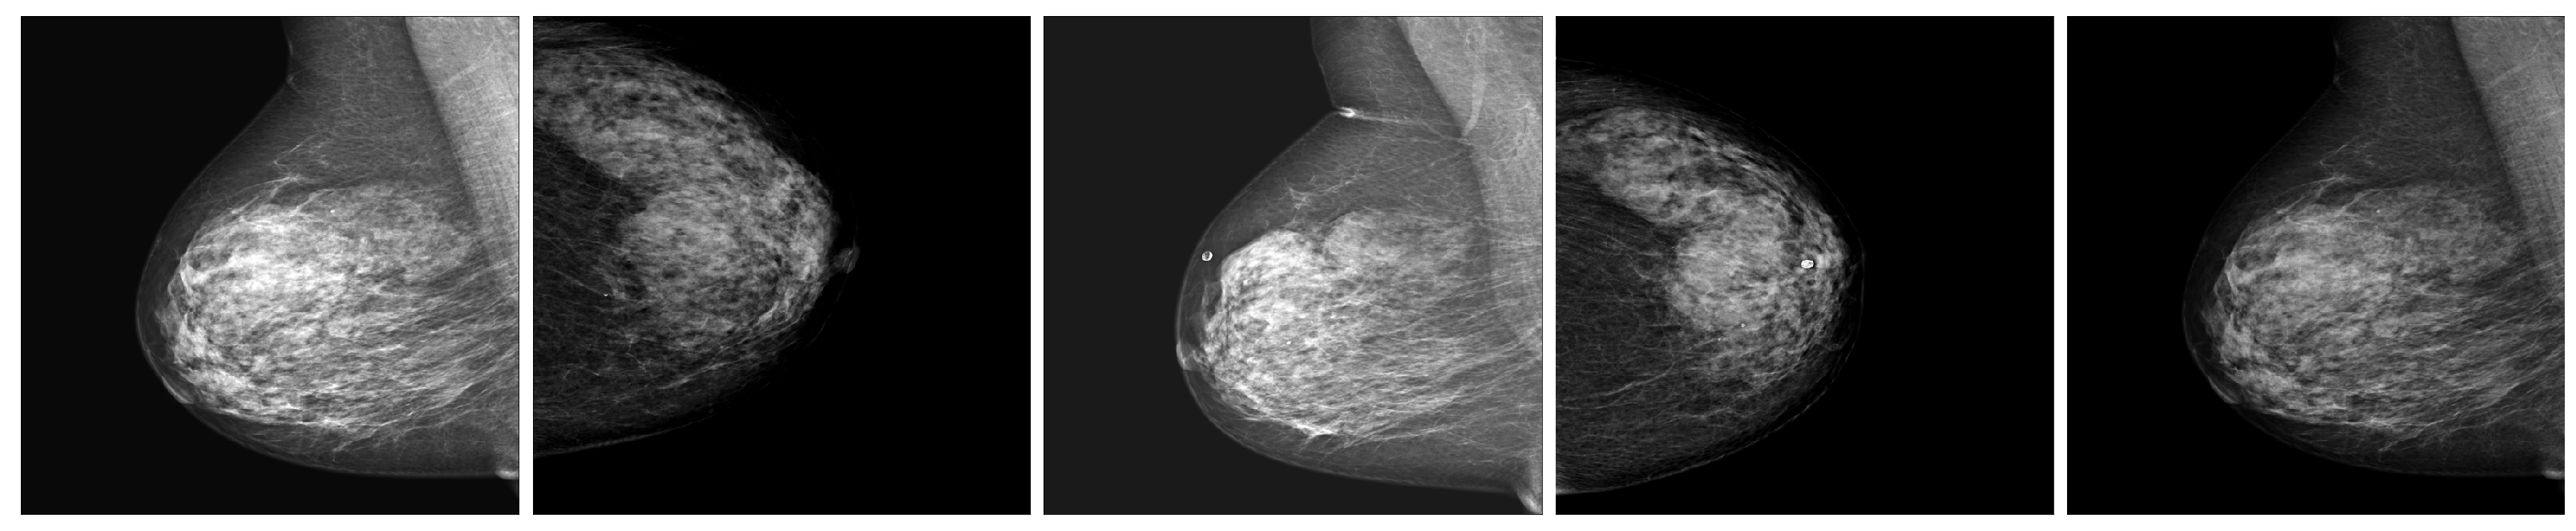

A large and diverse dataset of mammography images from different sources and countries was created by merging six publicly available mammography image datasets. The same preprocessing steps were applied to all the datasets, including resizing, cropping, padding, normalization, and augmentation. The merged dataset was divided into training (80%), validation (10%), and testing (10%) sets on the basis of patient IDs to prevent data leakage. Table 1 presents the summary statistics of the merged dataset. Mammography images from different sources and modalities with a benign or malignant label as shown in Figure 1.

Figure 1.

Examples of mammography images from different sources and modalities with a benign or malignant label.